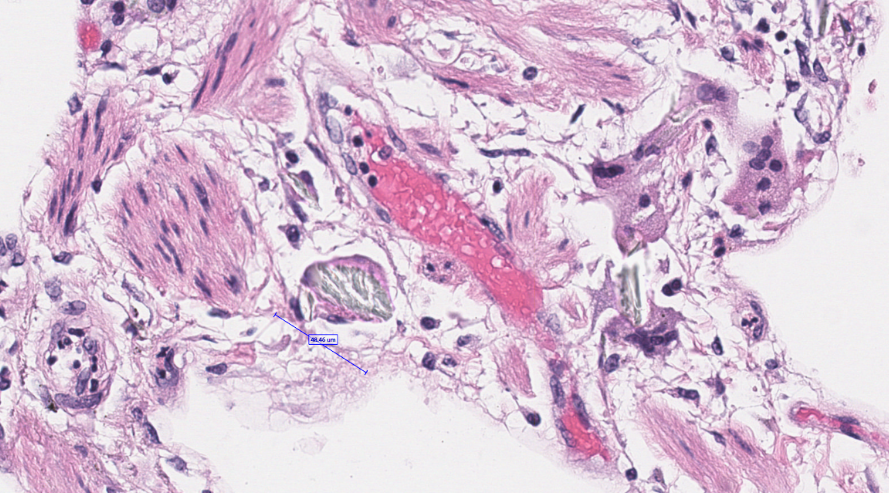

A startling biopsy. Severe acute TMA in a pt with suspected scleroderma renal crisis. Massive vascular thrombosis, mucoid intimal edema, and early onion skin change associated with severe cortical necrosis. #renalpath #nephrology #pathtwitter